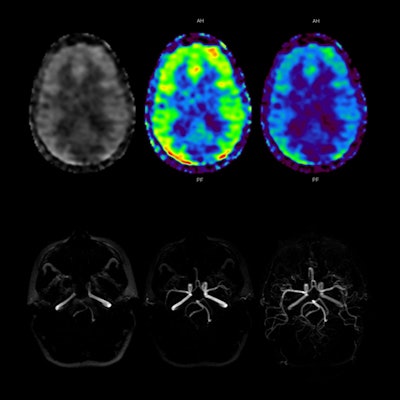

Two new advanced visualization techniques are cerebral spinal fluid (CSF) dynamic imaging (CSF Dynamic) and 3D arterial spin labeling (ASL) imaging. CSF Dynamic is a proprietary Toshiba technique that enables the visualization of spinal fluid movement using TimeSLIP, a noncontrast technique that's safer for patients.

Meanwhile, 3D ASL looks at blood flow and perfusion characteristics of the entire brain, and it can be performed without contrast in a single scan, unlike other techniques that require multiple scans.